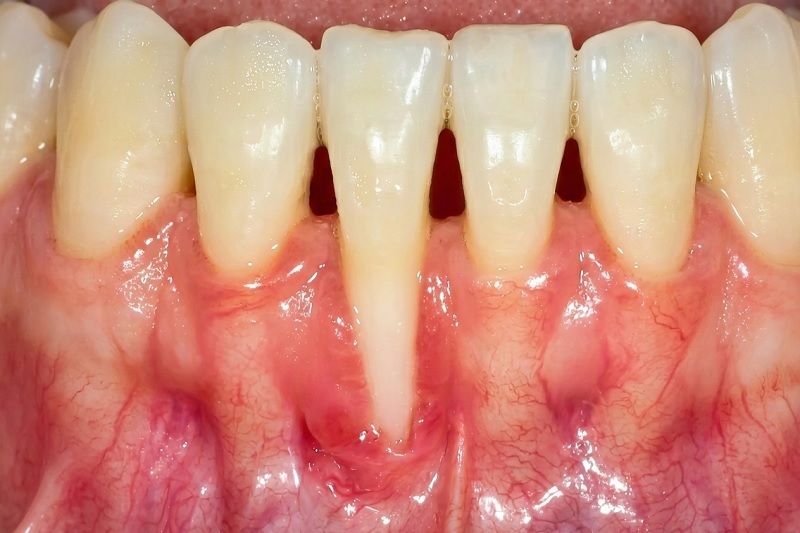

Tụt lợi (hay còn gọi là tụt nướu răng) là tình trạng bờ lợi di chuyển xuống phía chóp răng, làm lộ phần cổ răng hoặc chân răng vốn được che phủ và bảo vệ bởi mô lợi khỏe mạnh. Khi hiện tượng này xảy ra, răng thường có cảm giác “dài ra” hơn so với trước, đồng thời vùng cổ răng trở nên nhạy cảm rõ rệt.

Khi tụt lợi xảy ra, răng thường có cảm giác “dài ra” hơn so với trước.

Một đặc điểm khiến tụt lợi dễ bị bỏ sót là bệnh tiến triển chậm và âm thầm. Trong giai đoạn đầu, người bệnh có thể chỉ cảm thấy ê buốt nhẹ hoặc nhận thấy răng trông hơi dài hơn, nhưng không đau rõ rệt. Theo thời gian, khi phần chân răng lộ ra nhiều hơn, các biến chứng mới dần xuất hiện.

Tụt lợi không chỉ ảnh hưởng đến thẩm mỹ nụ cười mà còn tác động trực tiếp đến sức khỏe răng miệng. Khi chân răng bị lộ, lớp men bảo vệ không còn, răng dễ bị ê buốt khi ăn đồ nóng, lạnh, chua hoặc ngọt. Đồng thời, nguy cơ sâu chân răng và viêm nhiễm vùng cổ răng tăng lên rõ rệt.